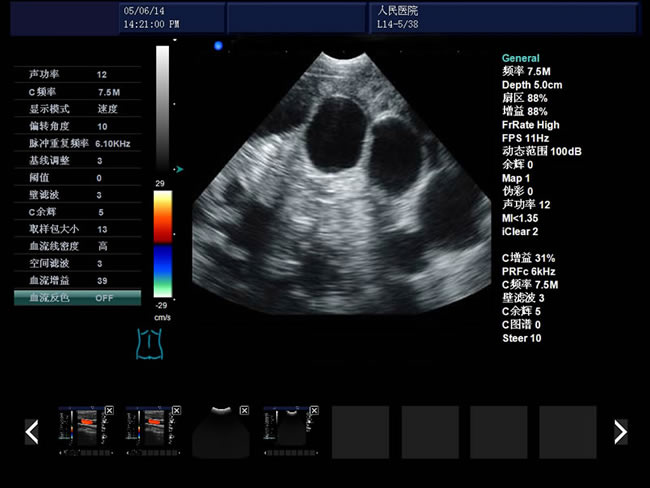

S8 彩色多普勒獸用超聲診斷儀

• S8彩色多普勒獸用超聲診斷儀是徐州市大為電子設備有限公司推出的一款全新的彩色超聲診斷儀器。

血流圖像:頻譜:B/D、B/C/D CFM:B|C|D、B|C|M、B|C雙實時、PW、CFM、CPA

彩色血流圖像調節參數:多普勒頻率、取樣框位置和大小、基線、彩色增益、偏轉角度、壁濾波、累積次數等。

1、檢查母豬的空懷,降低無效飼養的功效早已深入人心

2、用B超監測可及早準確掌握妊娠母豬頭數,較高的早期妊娠診斷準確率較好的保證了均衡生產

3、探查時間短、無應激、準確率高,而且產生巨大的生產應用價值